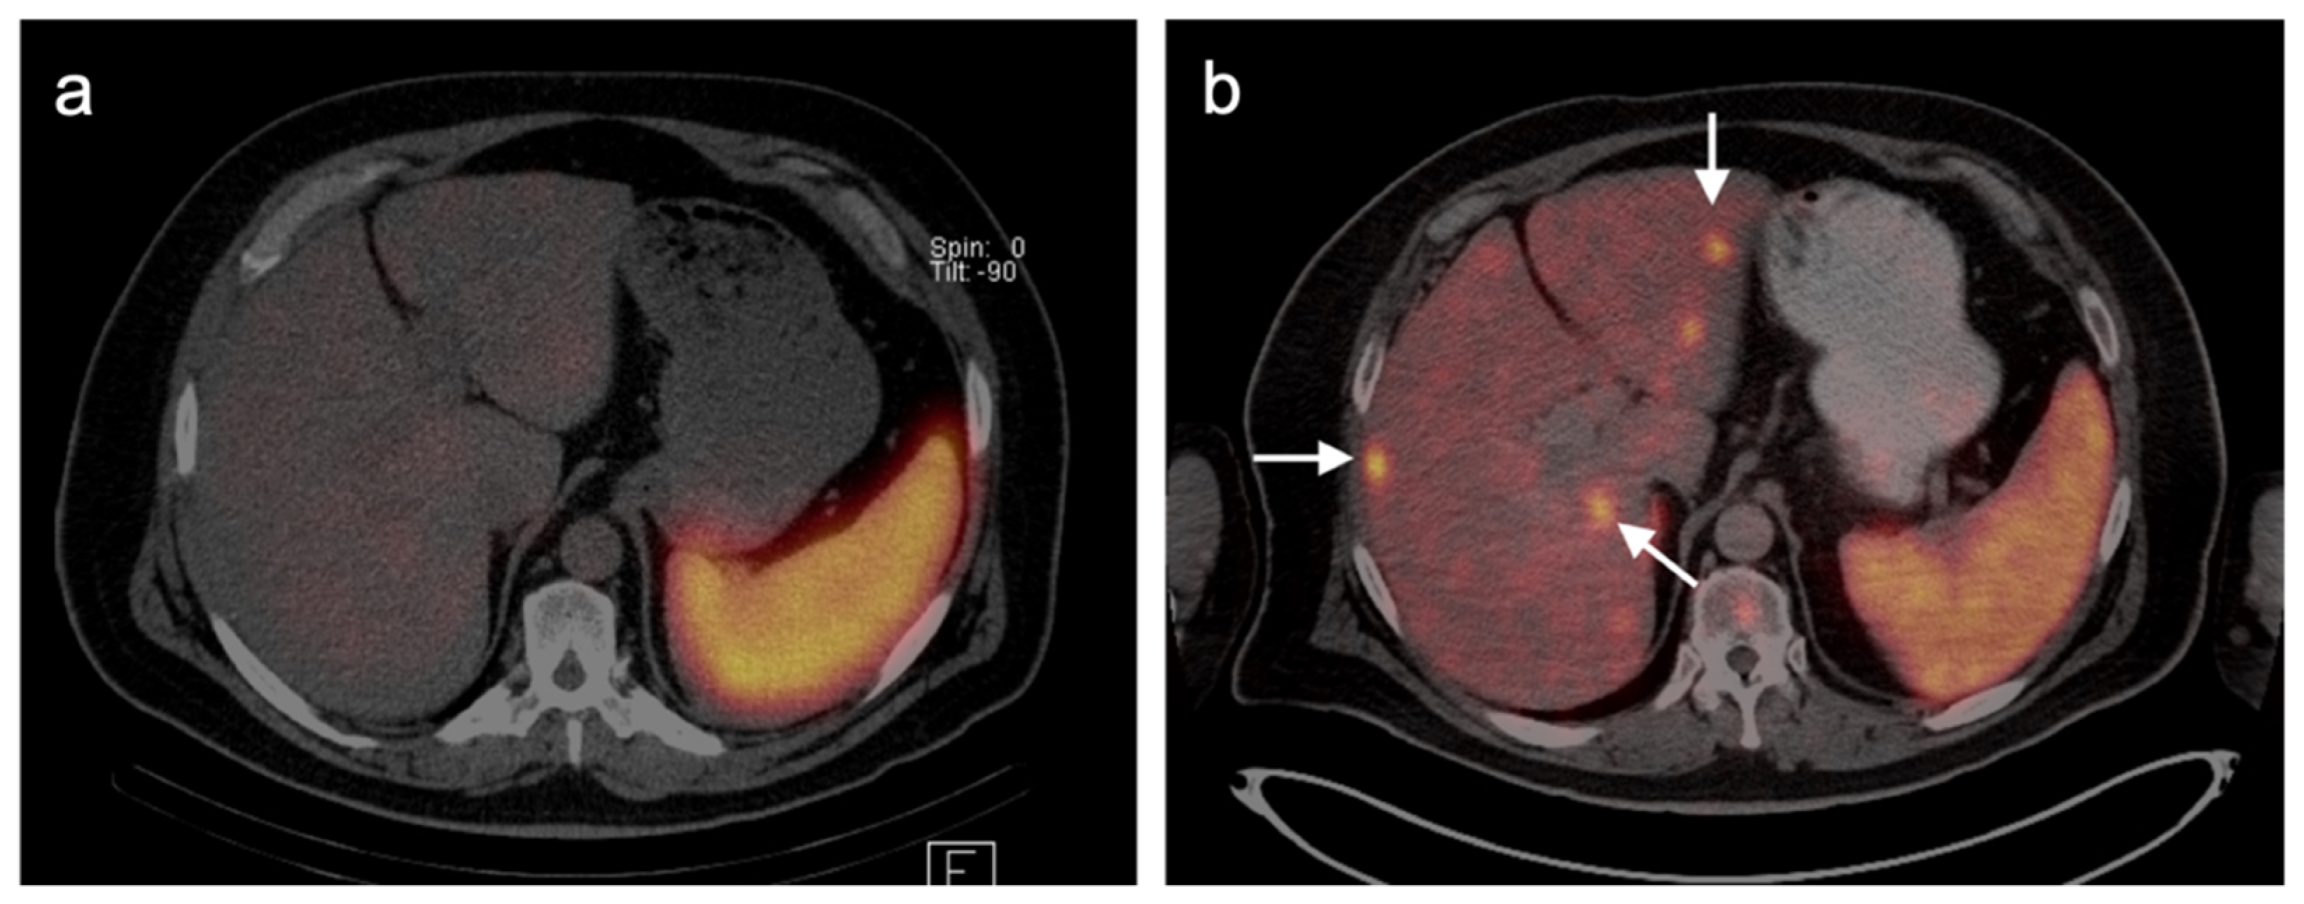

- Orcurto, V.; Denys, A.; Voelter, V.; Schalenbourg, A.; Schnyder, P.; Zografos, L.; Leyvraz, S.; Delaloye, A.B.; Prior, J. 18F-fluorodeoxyglucose positron emission tomography/computed tomography and magnetic resonance imaging in patients with liver metastases from uveal melanoma. Melanoma Res. 2012, 22, 63–69. [Google Scholar] [CrossRef] [PubMed]